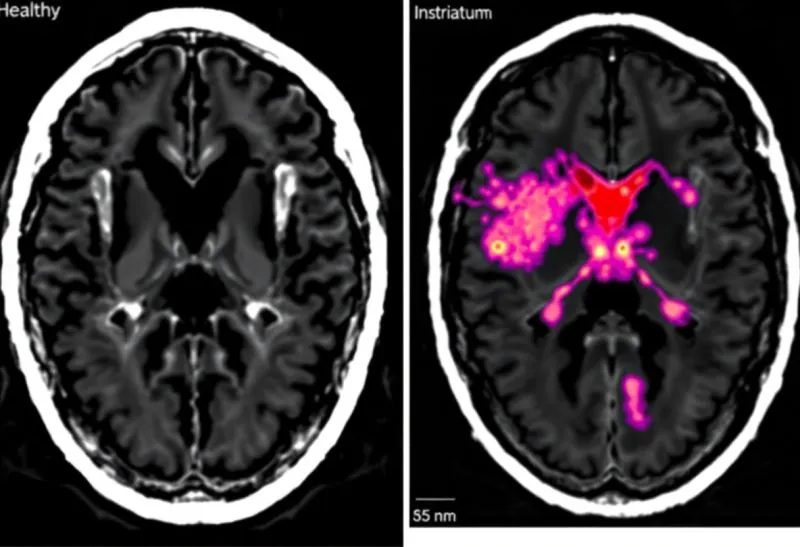

➡️ Résultat : chez les jeunes, cette surstimulation provoquerait une inflammation chronique du striatum, altérant durablement le circuit de la récompense (visible en neuro-imagerie).

❌ L'image associée a été générée en quelques secondes avec un outil d'IA ce matin

2️⃣ Une image avec un cerveau qui s'allume, "ça rend plus crédible"